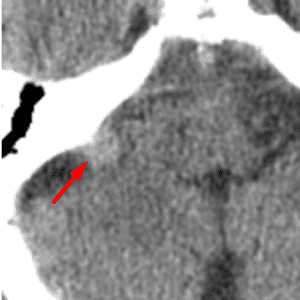

Calcific Scleral Plaques

Mimicking a foreign body